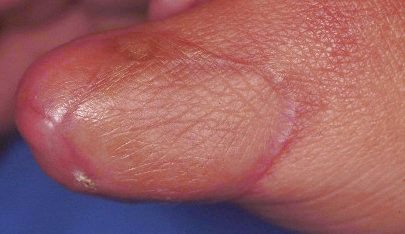

Circumferential router injury...

Late result.